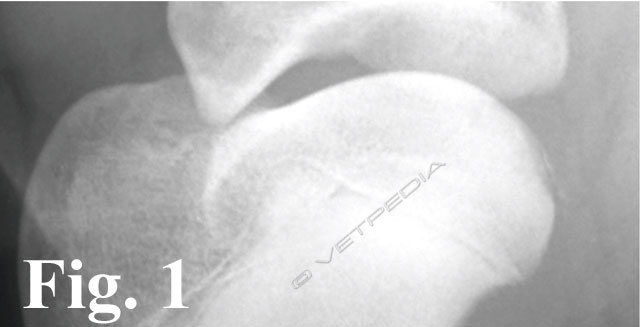

Alla visita ortopedica apprezziamo algia all’esecuzione dei movimenti passivi dell’articolazione. Con il cronicizzarsi della lesione osserviamo un diverso grado di ipomiotrofia dei muscoli della spalla. Il sospetto diagnostico emesso dalla visita clinica viene confermato mediante l’esecuzione di uno studio radiografico dell’articolazione della spalla. Per emettere una diagnosi è generalmente sufficiente eseguire una proiezione medio-laterale della spalla, avendo l’accortezza di esercitare una trazione sulla zampa in modo da scostare l’articolazione dalla sovrapposizione radiografica dello sterno. Considerando la frequente bilateralità della lesione, è doveroso eseguire un controllo dell’arto contro laterale, in modo da non trascurare quelle lesioni ancora clinicamente asintomatiche o paucisintomatiche. L’esame radiografico evidenzia un difetto del profilo del terzo caudale della testa omerale (Fig. 3). In alcuni casi è possibile visualizzare il lembo osteocondrale sollevato ma ancora in sede (vedi Fig. 1), in altri casi si può osservare solo un aumento della radiotrasparenza dell’osso subcondrale, più o meno esteso. Alcune forme iniziali di osteocondrosi (OC), non ancora evolute in osteocondrite dissecante (OCD), si manifestano radiograficamente come dei piccoli appiattimenti del profilo tondo della testa omerale, senza modificazioni della densità omogenea sub condrale (Fig. 4).

La corretta diagnosi di queste forme iniziali ci consente di indirizzare il paziente verso un approccio chirurgico o conservativo. In caso di diagnosi di OC, è consigliabile monitorare radiograficamente la lesione, con controlli a distanza di circa 2/3 settimane, in modo da valutarne l’evoluzione: guarigione spontanea versus formazione e sollevamento del lembo osteocondrale. Nei casi in cui la lesione è localizzata medialmente, la proiezione medio-laterale neutra potrebbe non consentirci di evidenziare il difetto osteocondrale o di sottostimarne l’estensione (Fig. 5a). E’ consigliabile a tal proposito eseguire una proiezione medio-laterale con rotazione esterna dell’arto, in modo da esporre al fascio radiogeno tangente anche le lesioni localizzate nel comparto mediale (Fig. 5b). Un’altra evenienza è rappresentata dalla migrazione del lembo osteocondrale che, come precedentemente accennato, nei casi più fortunati potrebbe andare incontro a riassorbimento spontaneo oppure comportarsi da “topo” o “tofo” articolare (Fig. 6). La sede dove più frequentemente tende a localizzarsi è rappresentata dal recesso caudale dell’articolazione (vedi Fig. 2), in casi meno fortunati potrebbe migrare nel comparto craniale, più precisamente nella doccia bicipitale, e determinare un’irritazione meccanica al tendine del muscolo bicipite brachiale. In quest’ultimo caso i sintomi dipenderanno dallo sviluppo di una tenosinovite bicipitale.